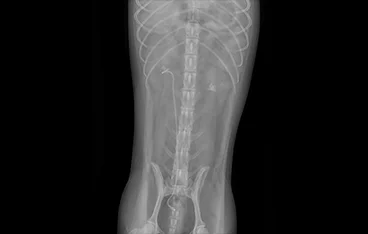

• TECA+LBO 수술 전

TECA+LBO 수술 후